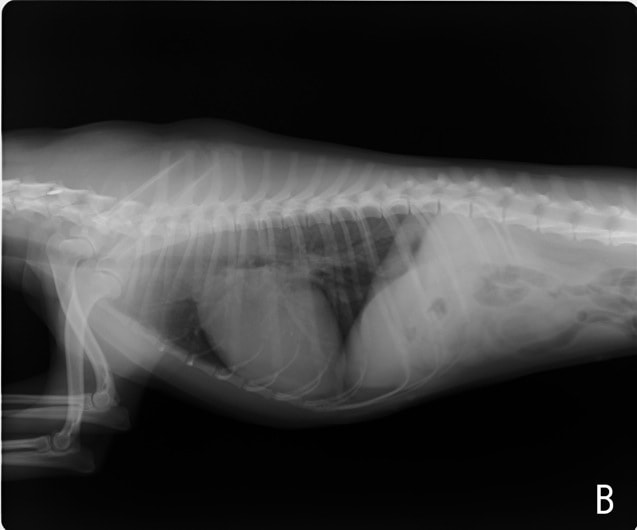

A:胸部レントゲン写真 側面像

左側胸壁心尖部領域を最強点とするLevine 5/6の収縮期性心雑音が聴取された。安静時にも咳が認められる。胸部レントゲン検査において重度の心拡大が及び肺水腫が認められた。超音波検査では、重度の僧帽弁閉鎖不全、三尖弁閉鎖不全が認められた。三尖弁逆流速度から肺高血圧症が示唆された。ACE阻害薬、ピモベンダン、硝酸イソソルビド徐放剤、ベラプロストナトリウム、利尿剤としてフロセミド及びスピロノラクトンを用いて治療を行っている。